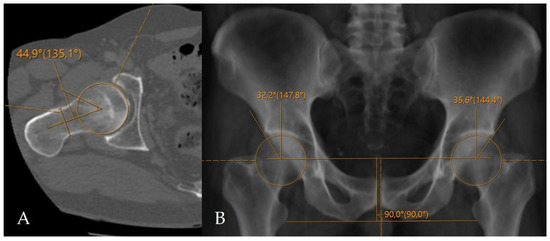

Figure 2.

Application of conventional angular measurement methods on a radiology workstation. (A) Measurement of the alpha angle on axial oblique CT reformats. (B) Measurement of the LCEA on a CT-based virtual pelvic radiograph.